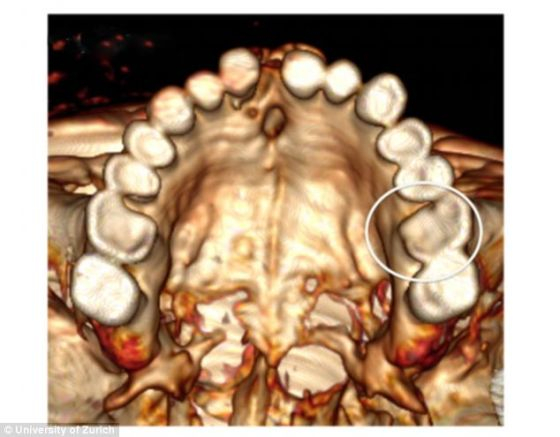

“奥茨”的牙齿严重磨损,圆圈内的臼齿在颚侧出现裂口,对面的臼齿同样出现严重磨损,只有颚侧的牙釉质仍保持完整

塞勒的研究结果显示“奥茨”的后臼齿缺少牙周支撑组织,几乎一直到牙根部都存在这种现象。“奥茨”可能从不清洁牙齿,不过,他的饮食结构有助于牙齿进行自清洁。研究表明“奥茨”的牙齿腐烂与大量摄入多淀粉食物有关,例如面包和麦片粥。由于农业的兴起,新石器时代的古人普遍食用面包。

由于含有污染物和碾谷磨的微小碎片,“奥茨”所吃的食物导致牙齿磨损严重。一颗门牙受损严重以及其他身体部位的损伤说明“奥茨”的生活麻烦不断。他的这颗门牙出现严重的机械性创伤,褪色现象至今仍清晰可见。此外,他的一颗臼齿没有牙尖,可能是在吃麦片粥时被粥里的小石子咯掉了。